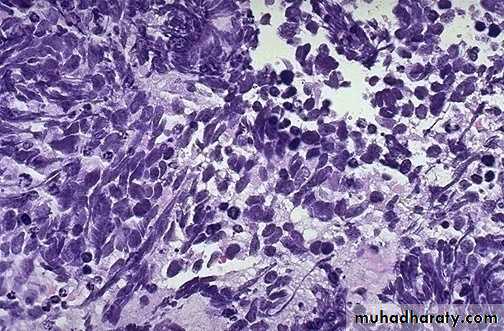

2,Oat cell carcinoma : Arises from neuroendocrine cells in the bronchial mucosa . Consist of small hyperchromatic cells similar to aot seeds. Arranges in sheetsBy E/M the cells contain neurosecretory granules

Oat cell carcinoma -Bronchus